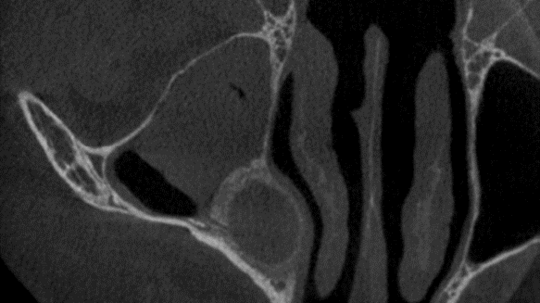

In direkter Nachbarschaft des Kiefers verlaufen wichtige Strukturen wie etwa Nerven und Gefäße. Um das Risiko einer Verletzung und die Ausdehnung der Operation so gering wie möglich zu halten, empfehlen wir in bestimmten Fällen vor dem Eingriff eine 3D-Röntgendiagnostik, bekannt als Digitale Volumentomographie (DVT). Diese Art der Bildgebung wird jedoch von den gesetzlichen Krankenkassen in der Regel nicht übernommen.

Als Alternative besteht die Möglichkeit, notwendige Schnittbildgebungen (MRT oder CT) in einer niedergelassenen radiologischen Praxis durchführen zu lassen. Dies kann nach einer Überweisung durch Ihre Hausärztin oder Ihren Hausarzt erfolgen. Der dabei erstellte Bilddatensatz kann dann zur Vorbesprechung mitgebracht werden, um die Operation optimal zu planen und durchzuführen.